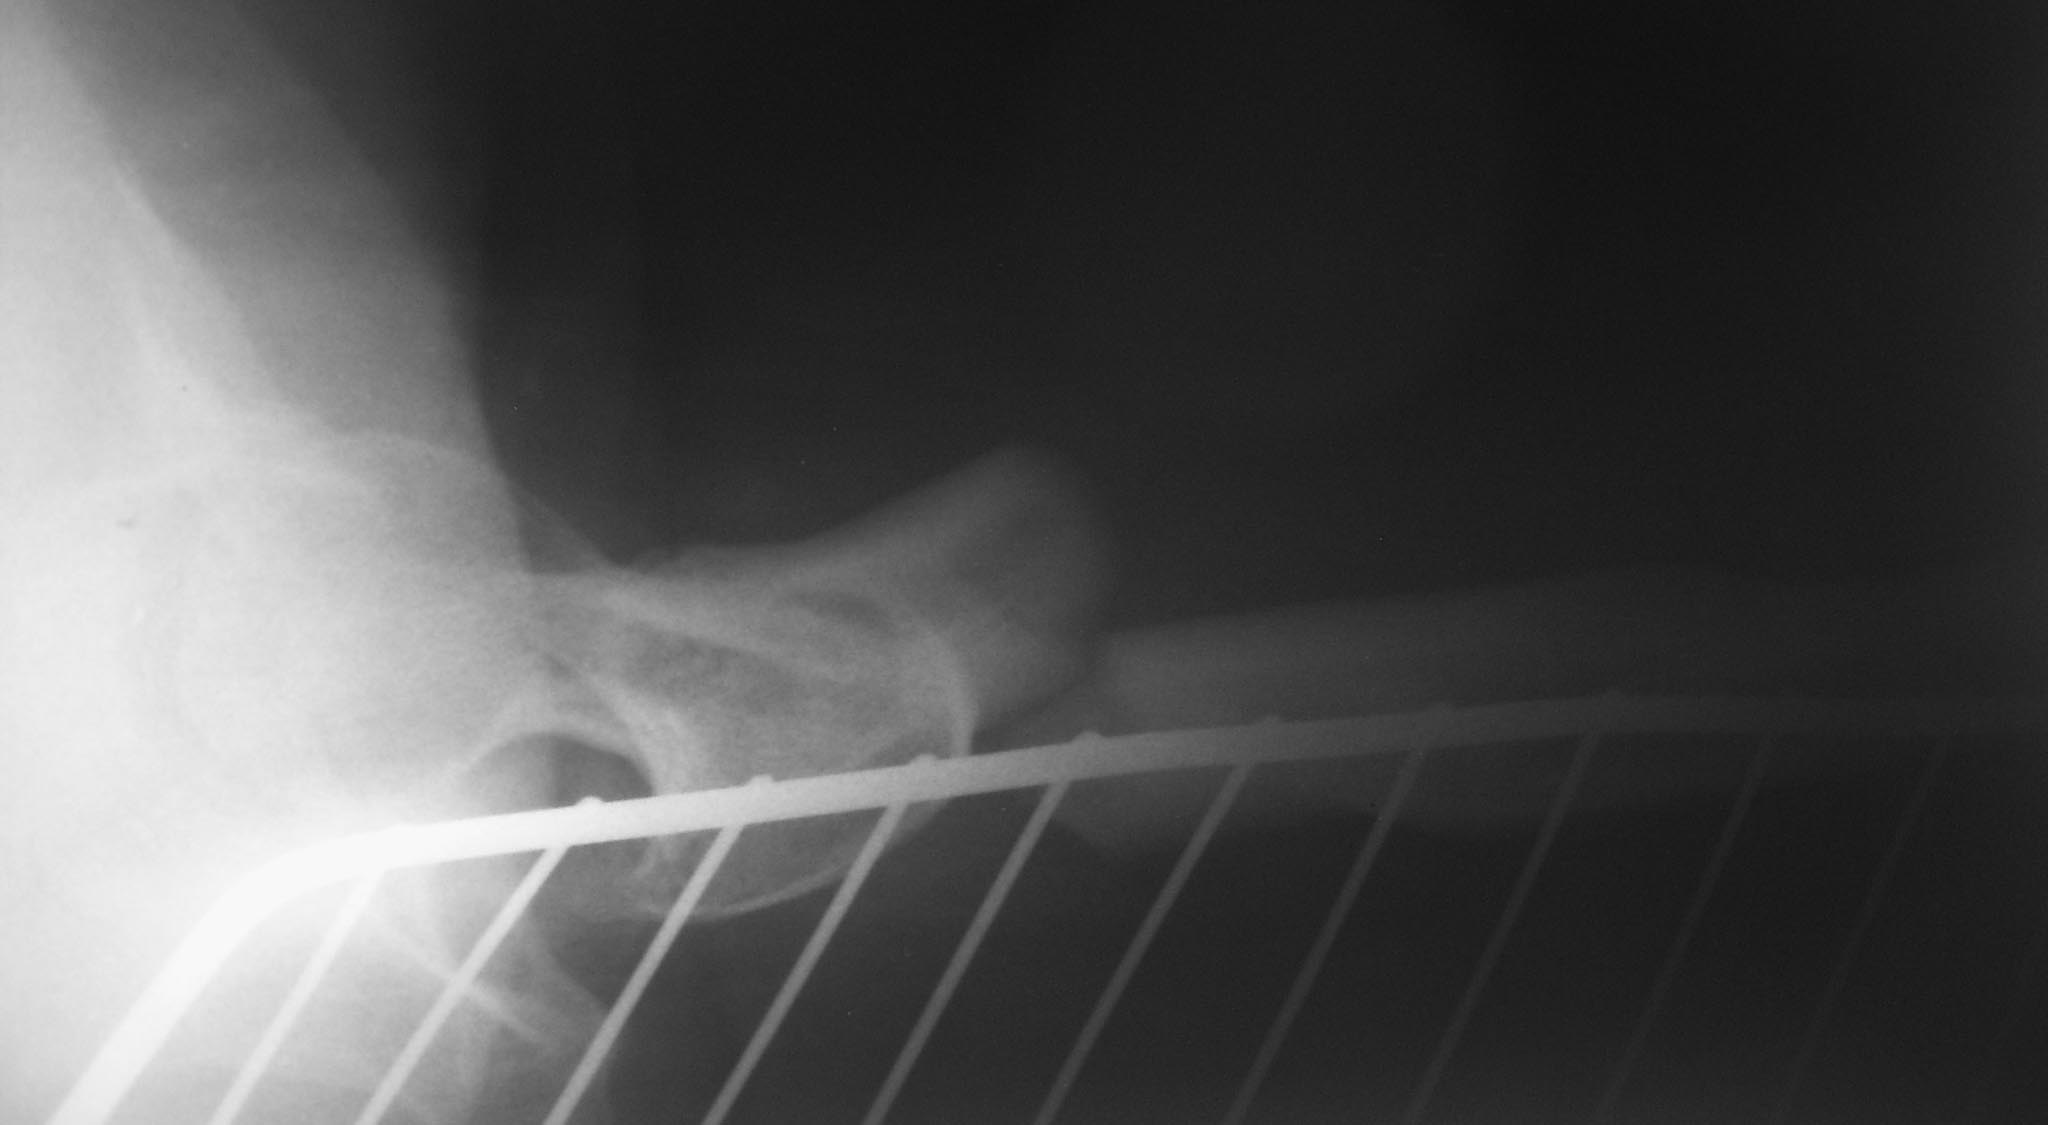

Доброе время суток.Поступила больная с поперечным переломом верхней

трети левого бедра по типу 32А3.

На рентгенорафии отмечается подвывих головки левого бедра II степени по

Crowe. И узкий и извитой канал бедра. Учитывая вывих головки бедра и

укорочение около 7-ми см левой нижней конечности. Мы предполагаем

остеосинтез бедра и через год эндопротезирование тазобедренного сустава.

Какой остеосинтез предподчтителен Итрамедуллярный

блокированный или накостная пластина? Спасибо за участие.